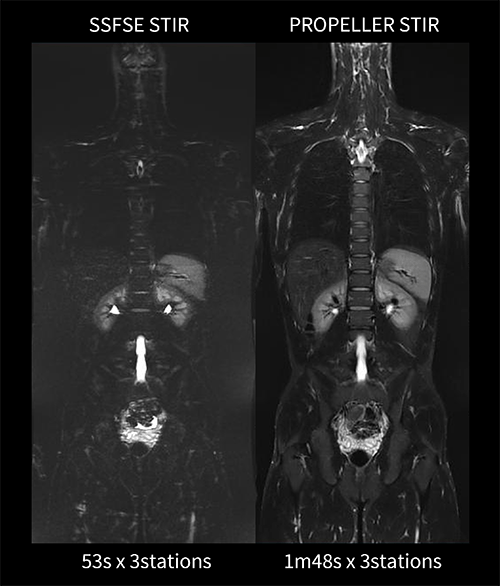

転移検索プロトコルは、日本磁気共鳴医学会より提唱されている「前立腺癌の骨転移検出のための全身MRI撮像の細則」に従いプロトコルを作成しているが、当院では、WBDWIとFusion(DWI-T2WI)画像だけでなく、高分解能のT2WIも併せて読影したいという放射線科医の要望で全身T2WIの横断像をシングルショットFSE(以下SSFSE)で追加撮像している。熱源検索プロトコルは、LAVA-Flex、in phase、out of phaseの代わりに血管炎や筋炎等の炎症所見を広範囲で捉えることのできるSTIRを冠状断で撮像している。従来はSTIRをSSFSEで撮像していたためブラーリングや呼吸のアーチファクトの影響を強く受けていたが、PROPELLERを用いることで自由呼吸下でも高分解能・高SNRで全身のSTIRを撮像できることが可能となった(図7)。

Architect_Okazakishimin02_10.png

図7 STIR撮像におけるSSFSEとPROPELLERの比較